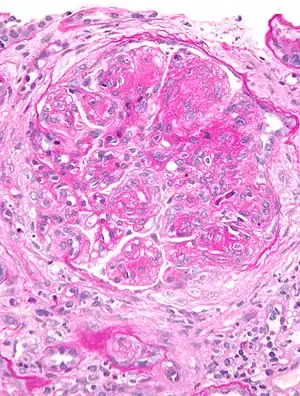

Glomerulonefrite membranoproliferativa

GlomeruloNefrite MembranoProliferativa (GNMP) é uma doença renal caracterizada por lesão da membrana basal e mesângios dos glomérulos dos néfrons, partes dos rins essenciais para a boa filtração do plasma sanguíneo.[1]

O achado de microscopia óptica mais característico é a hipercelularidade e duplicação da membrana basal glomerular. Em todos os casos existe deposição do sistema complemento nos glomérulos e depósito de imunoglobulinas ocorre menos freqüentemente.